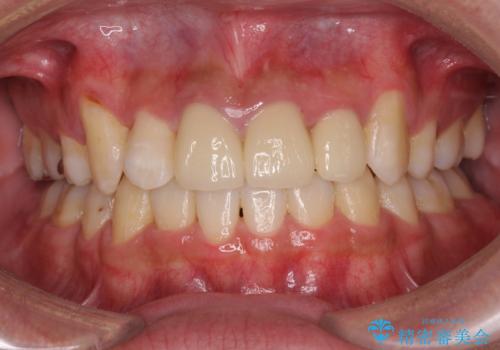

デコボコと変色した前歯 抜歯矯正と審美歯科治療

前歯の歯列が整ったことで、歯磨きが大変やりやすくなり、患者様には大変満足していただけました。